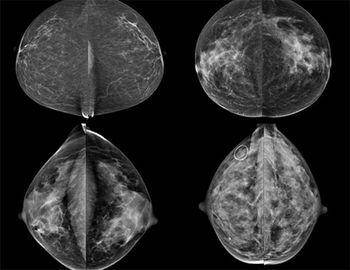

49-year-old patient presented for bilateral screening mammogram as well as bilateral screening ultrasound due to dense breast tissue.